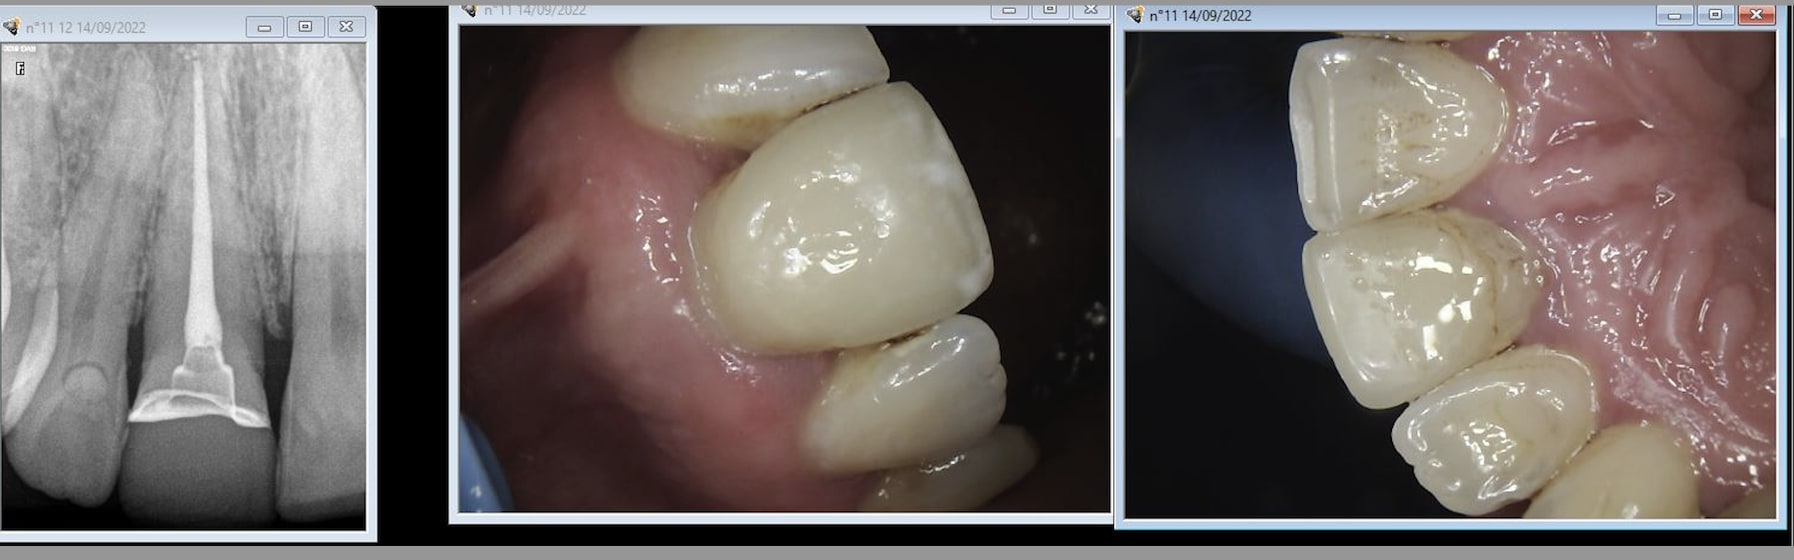

Alternative endo couronne cerec. Collée sans digue en 2007, sans aides optiques, sans composite chauffé, toujours en place.

Vphjlmjkzw8bg1wxgwyht8un71xj - Eugenol